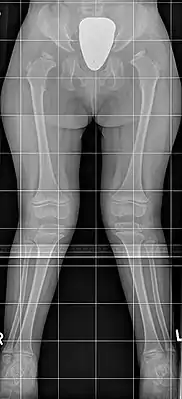

![]() Синдром Моркио: на рентгенограмме с двух сторон отмечается укорочение шейки бедра, в результате чего уменьшается поперечник таза; крылья подвздошных костей неправильной формы; характерна вальгусная деформация нижних конечностей | |